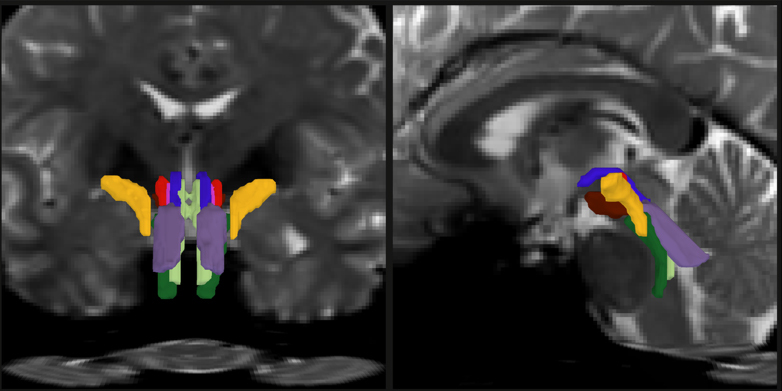

In a new study, a team of MIT, Harvard University, and Massachusetts General Hospital researchers unveil AI-powered software capable of automatically segmenting eight distinct bundles in any diffusion MRI sequence.

In the open-access study, published Feb. 6 in the Proceedings of the National Academy Sciences, the research team led by MIT graduate student Mark Olchanyi reports that their BrainStem Bundle Tool (BSBT), which they’ve made publicly available, revealed distinct patterns of structural changes in patients with Parkinson’s disease, multiple sclerosis, and traumatic brain injury, and shed light on Alzheimer’s disease as well. Moreover, the study shows, BSBT retrospectively enabled tracking of bundle healing in a coma patient that reflected the patient’s seven-month road to recovery.